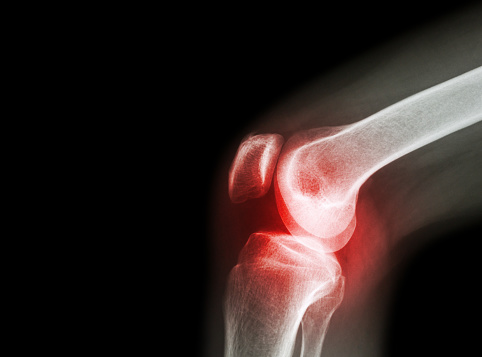

Elbow arthritis is a painful condition that may be caused by overuse, trauma, or simply just getting older. Much like other joints of the body, the elbow joint is lined with cartilage that acts to provide support, allows for flexibility of movement, and help to protect the end of the joint from constant friction. However, ...click here to read more